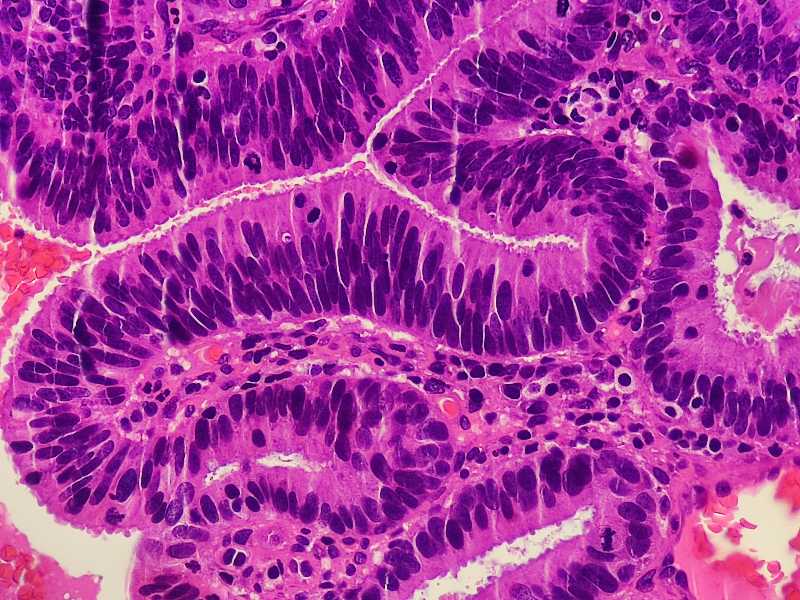

女49岁宫颈糜烂,HPV16和HPV18阳性。宫颈腺体异型原位还是浸润?

腺癌